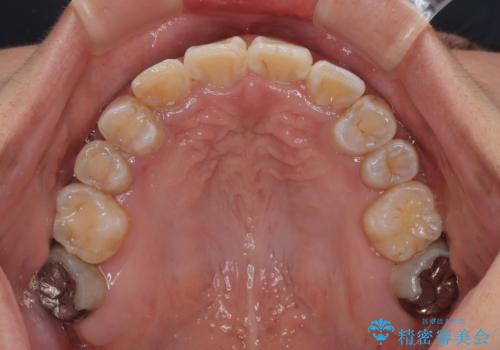

下顎は第二小臼歯を抜歯したため、治療期間が長期化すると思われましたが、大臼歯が後方に傾斜していたため、容易にスペースを閉じることができ、2年強で治療を終えることができました。